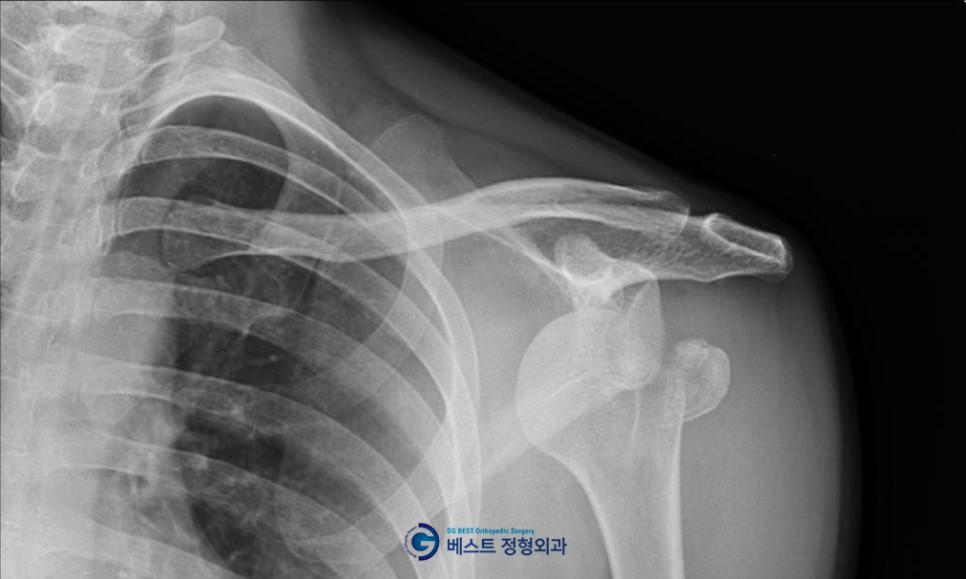

어깨 질환으로 고통받는 환자는 점점 늘고 있습니다. 오십견은 특별한 외상이나 충격 없이 어깨 관절이 딱딱해져 통증이 생기는 질환입니다. 예전에는 50대 이상에서 많이 발견된다고 해서 붙여진 이름이지만 최근에는 30대부터 70대까지 발생하는 연령층이 다양해졌습니다. 오십견의 정확한 의학적 진단명은 유착성 관절낭염 또는 동결견입니다.

오십견은 뚜렷한 원인을 모르는 경우가 대부분이며 가벼운 외상 후 증상이 악화될 수도 있습니다. 무엇보다 50대가 대부분 차지했지만 최근에는 젊은 층에서도 늘고 있어 주의가 필요해졌습니다. 오십견 증상으로 만세 동작을 하지 못하거나 뒷짐을 잡는 동작이 어려울 경우 의심해봐야 하며 팔을 바깥쪽으로 뻗거나 위로 올릴 때 특히 불편하다면 오십견 증상의 특징입니다.

대부분의 오십견은 다른 원인으로 인해 어깨관절 윤활주머니인 관절낭에 염증이 생겨 관절낭 구축이 발생하게 된 것입니다. 목이나 어깨의 결림이나 피로감으로 시작되는 오십견의 증상은 심한 경우 팔을 들었다 놨다 할 때에도 심한 통증을 느낍니다. 잘못된 어깨 운동도 오십견 발생에 영향을 미칩니다.